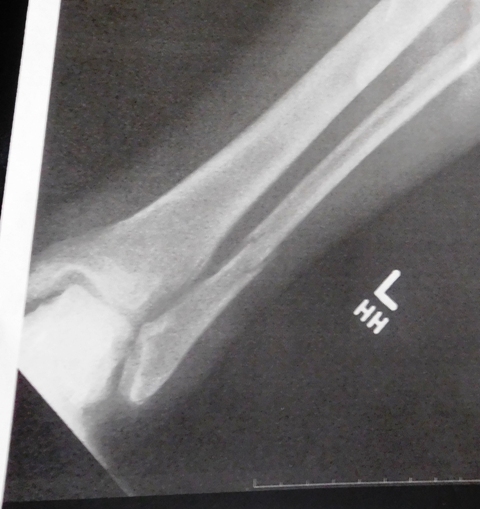

Oh, I asked for and got a copy of my first x-ray showing my broken fibula.  Pretty cool, huh?